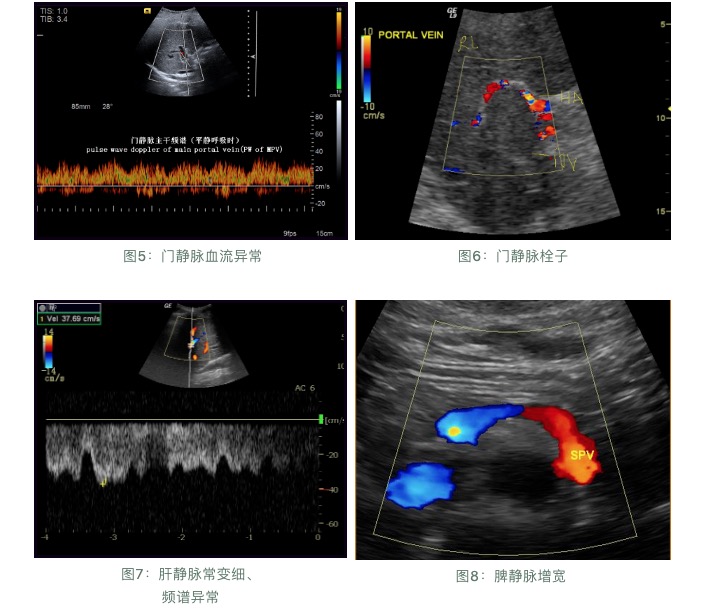

超聲檢查:

肝臟受病毒感染和發(fā)生炎癥后,就會(huì)造成肝臟內(nèi)部的結(jié)構(gòu)損傷,從局部的纖維化、結(jié)節(jié)性肝硬化到最后的全面硬化,超聲檢查是早期發(fā)現(xiàn)肝硬化的最直接指標(biāo)。